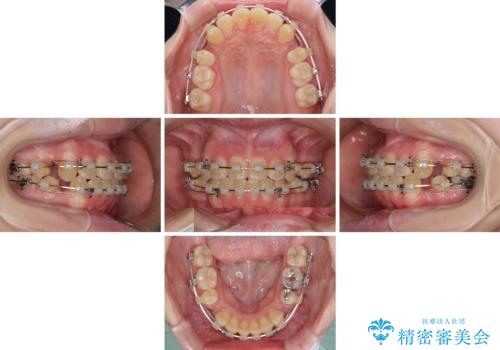

上下の出っ歯を治したい ワイヤー装置による抜歯矯正

- 上下前歯が前方に飛び出しているとのことで来院された患者様です。

上下左右第一小臼歯4本を抜歯して、積極的に口元を引っ込めるよう、ワイヤー装置にて矯正治療を行うこととしました。

口元の突出感は著しく改善され、横顔の印象が大きく変化しました。